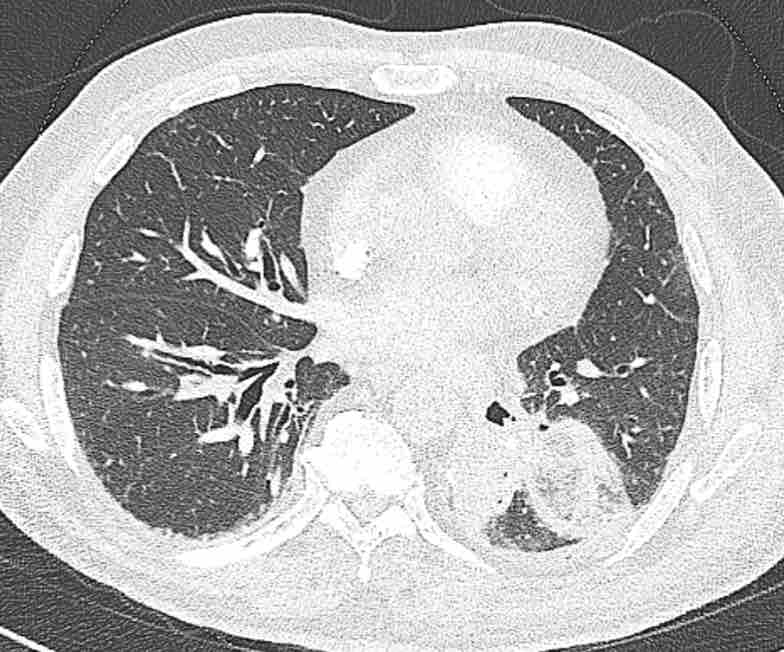

Cuộn qua các hình ảnh để quan sát khí quản phân chia thành phế quản chính phải và trái, sau đó tiếp tục phân chia thành các phế quản thùy và phế quản phân thùy.

Cuộn qua các hình ảnh để quan sát cách phổi được phân chia thành các phân thùy.